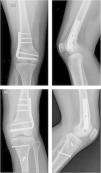

Paciente masculino 17años de edad que refiere que hace 4años, mientras realizaba actividad deportiva (fútbol), sufrió traumatismo sobre su rodilla izquierda, presentando fractura a nivel de la meseta tibial, por lo que le realizaron osteosíntesis con tornillos. Actualmente consulta por deformidad en valgo de la rodilla izquierda, acortamiento y rotación interna de la extremidad durante la marcha. Se realizan estudios radiográficos para valorar el estado de partes óseas (fig. 4); así mismo, se solicita telemetría de miembros inferiores para valorar el acortamiento de la extremidad afecta (fig. 5).